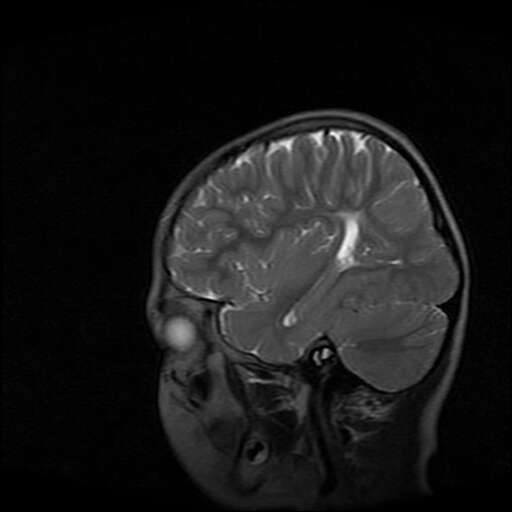

女,7岁,三岁才说话、走路。现智力尚可,走路不稳。临床怀疑大脑发育不全。

考虑 脑白质发育不良

脑折质变薄,双侧侧脑室稍扩张,支持考虑脑折质发育不良

侧脑室周围白质软化症。

考虑胼胝体发育不全,髓鞘形成不良。

支持考虑胼胝体发育不全,髓鞘形成不良。

脑裂畸形伴灰质异位

侧脑室周围白质数量减少,侧脑室不对称性扩大,左侧侧脑室后角呈方形改变,脑沟加深,结合临床考虑脑室周围白质软化症(pvl)。期待结果!

只看出灰质异位

支持脑白质发育不良。